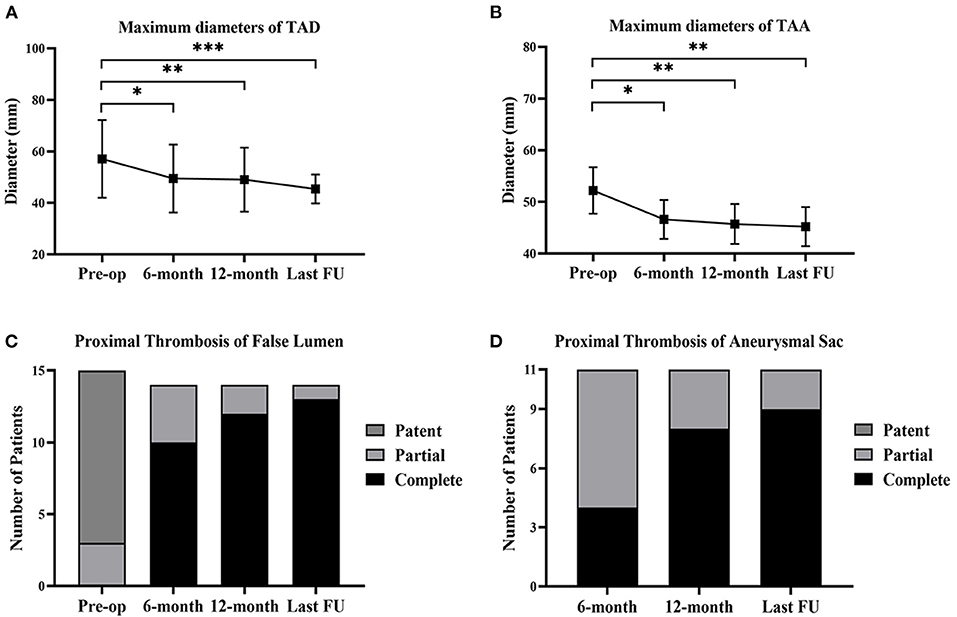

Compared with the preoperative conditions, the maximum aortic diameters were significantly decreased after the 6-month follow-up and remained stable at the last follow-up (Figures 6A,B). After implantation, the proximal complete thrombosis of the false lumen in patients with TAD was 10 (71.4%), 12 (85.7%), and 13 (92.9%) at the time of 6, 12 months, and the last follow-up (Figure 6C). The prevalence of complete thrombosis in aneurysmal sac increased from 4 (36.4%) at 6-month follow-up to 9 (81.8%) at the last follow-up (Figure 6D).

Figure 6. Aortic remodeling and proximal thrombosis of false lumen/aneurysmal sac at follow-up. (A) The changes of maximum diameters of TAD before the operation, at 6-month, 12-month, and the last follow-up. (B) The changes of maximum diameters of TAA before the operation, at 6-month, 12-month, and the last follow-up. (C) The proximal thrombosis of false lumen in TAD (n = 15) before the operation, at 6-month, 12-month, and the last follow-up. One patient suffered from retrograde type A aortic dissection after 3 months and received the total arch replacement. (D) The proximal thrombosis of aneurysmal sac in TAA (n = 11) at 6-month, 12-month, and the last follow-up. *p < 0.05; **p < 0.01; ***p < 0.001. TAD, thoracic aortic dissection; TAA, thoracic aortic aneurysm; FU, follow-up.